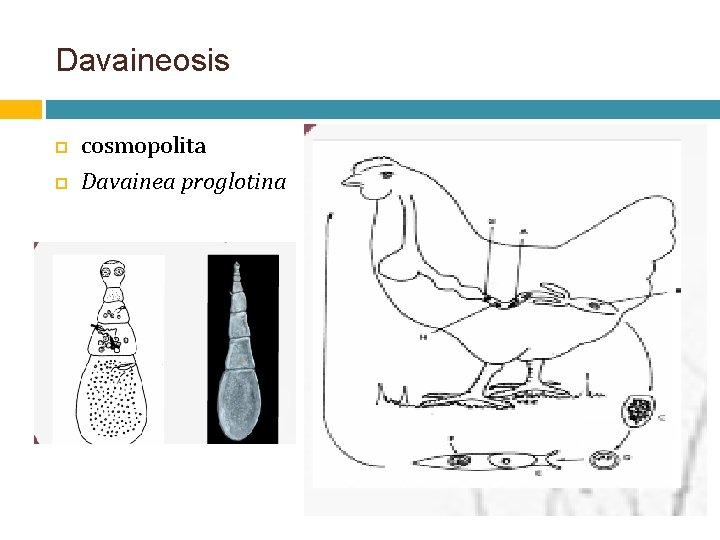

Davaineosis cosmopolita Davainea proglotina